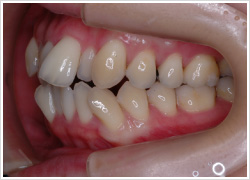

こうした患者さんでは歯列の中で凸凹があってはみ出たり、傾いたり、曲がって生えている歯、伸び出して他の歯よりも早くぶつかる歯などがあると口を閉じてきた時、こうした歯で強くぶつかるのを自然と避けて、上下の歯が合わさりやすい位置へずらして咬もうとする習慣が身に付いてしまっているのです。

術者が(顎関節に負担のかからない)本来の顎位へ誘導すると、この患者さんは傾いて生えた左上の親知らずが他の歯より先に下の歯とぶつかってちゃんと咬めていないことわかります。

この様にずれた状態で診断をすると、治療方針が変わってきます。当院では、正しい顎の位置で治療方針を立てます。